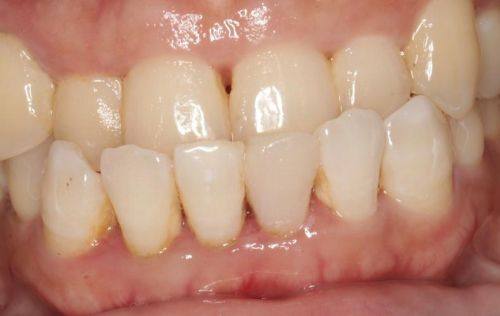

2. 牙齿矫正:提供传统金属矫正、金属自锁托槽、陶瓷半隐形矫治、全隐形透明牙套等正畸技术,能处理疑难复杂的畸形牙齿问题。